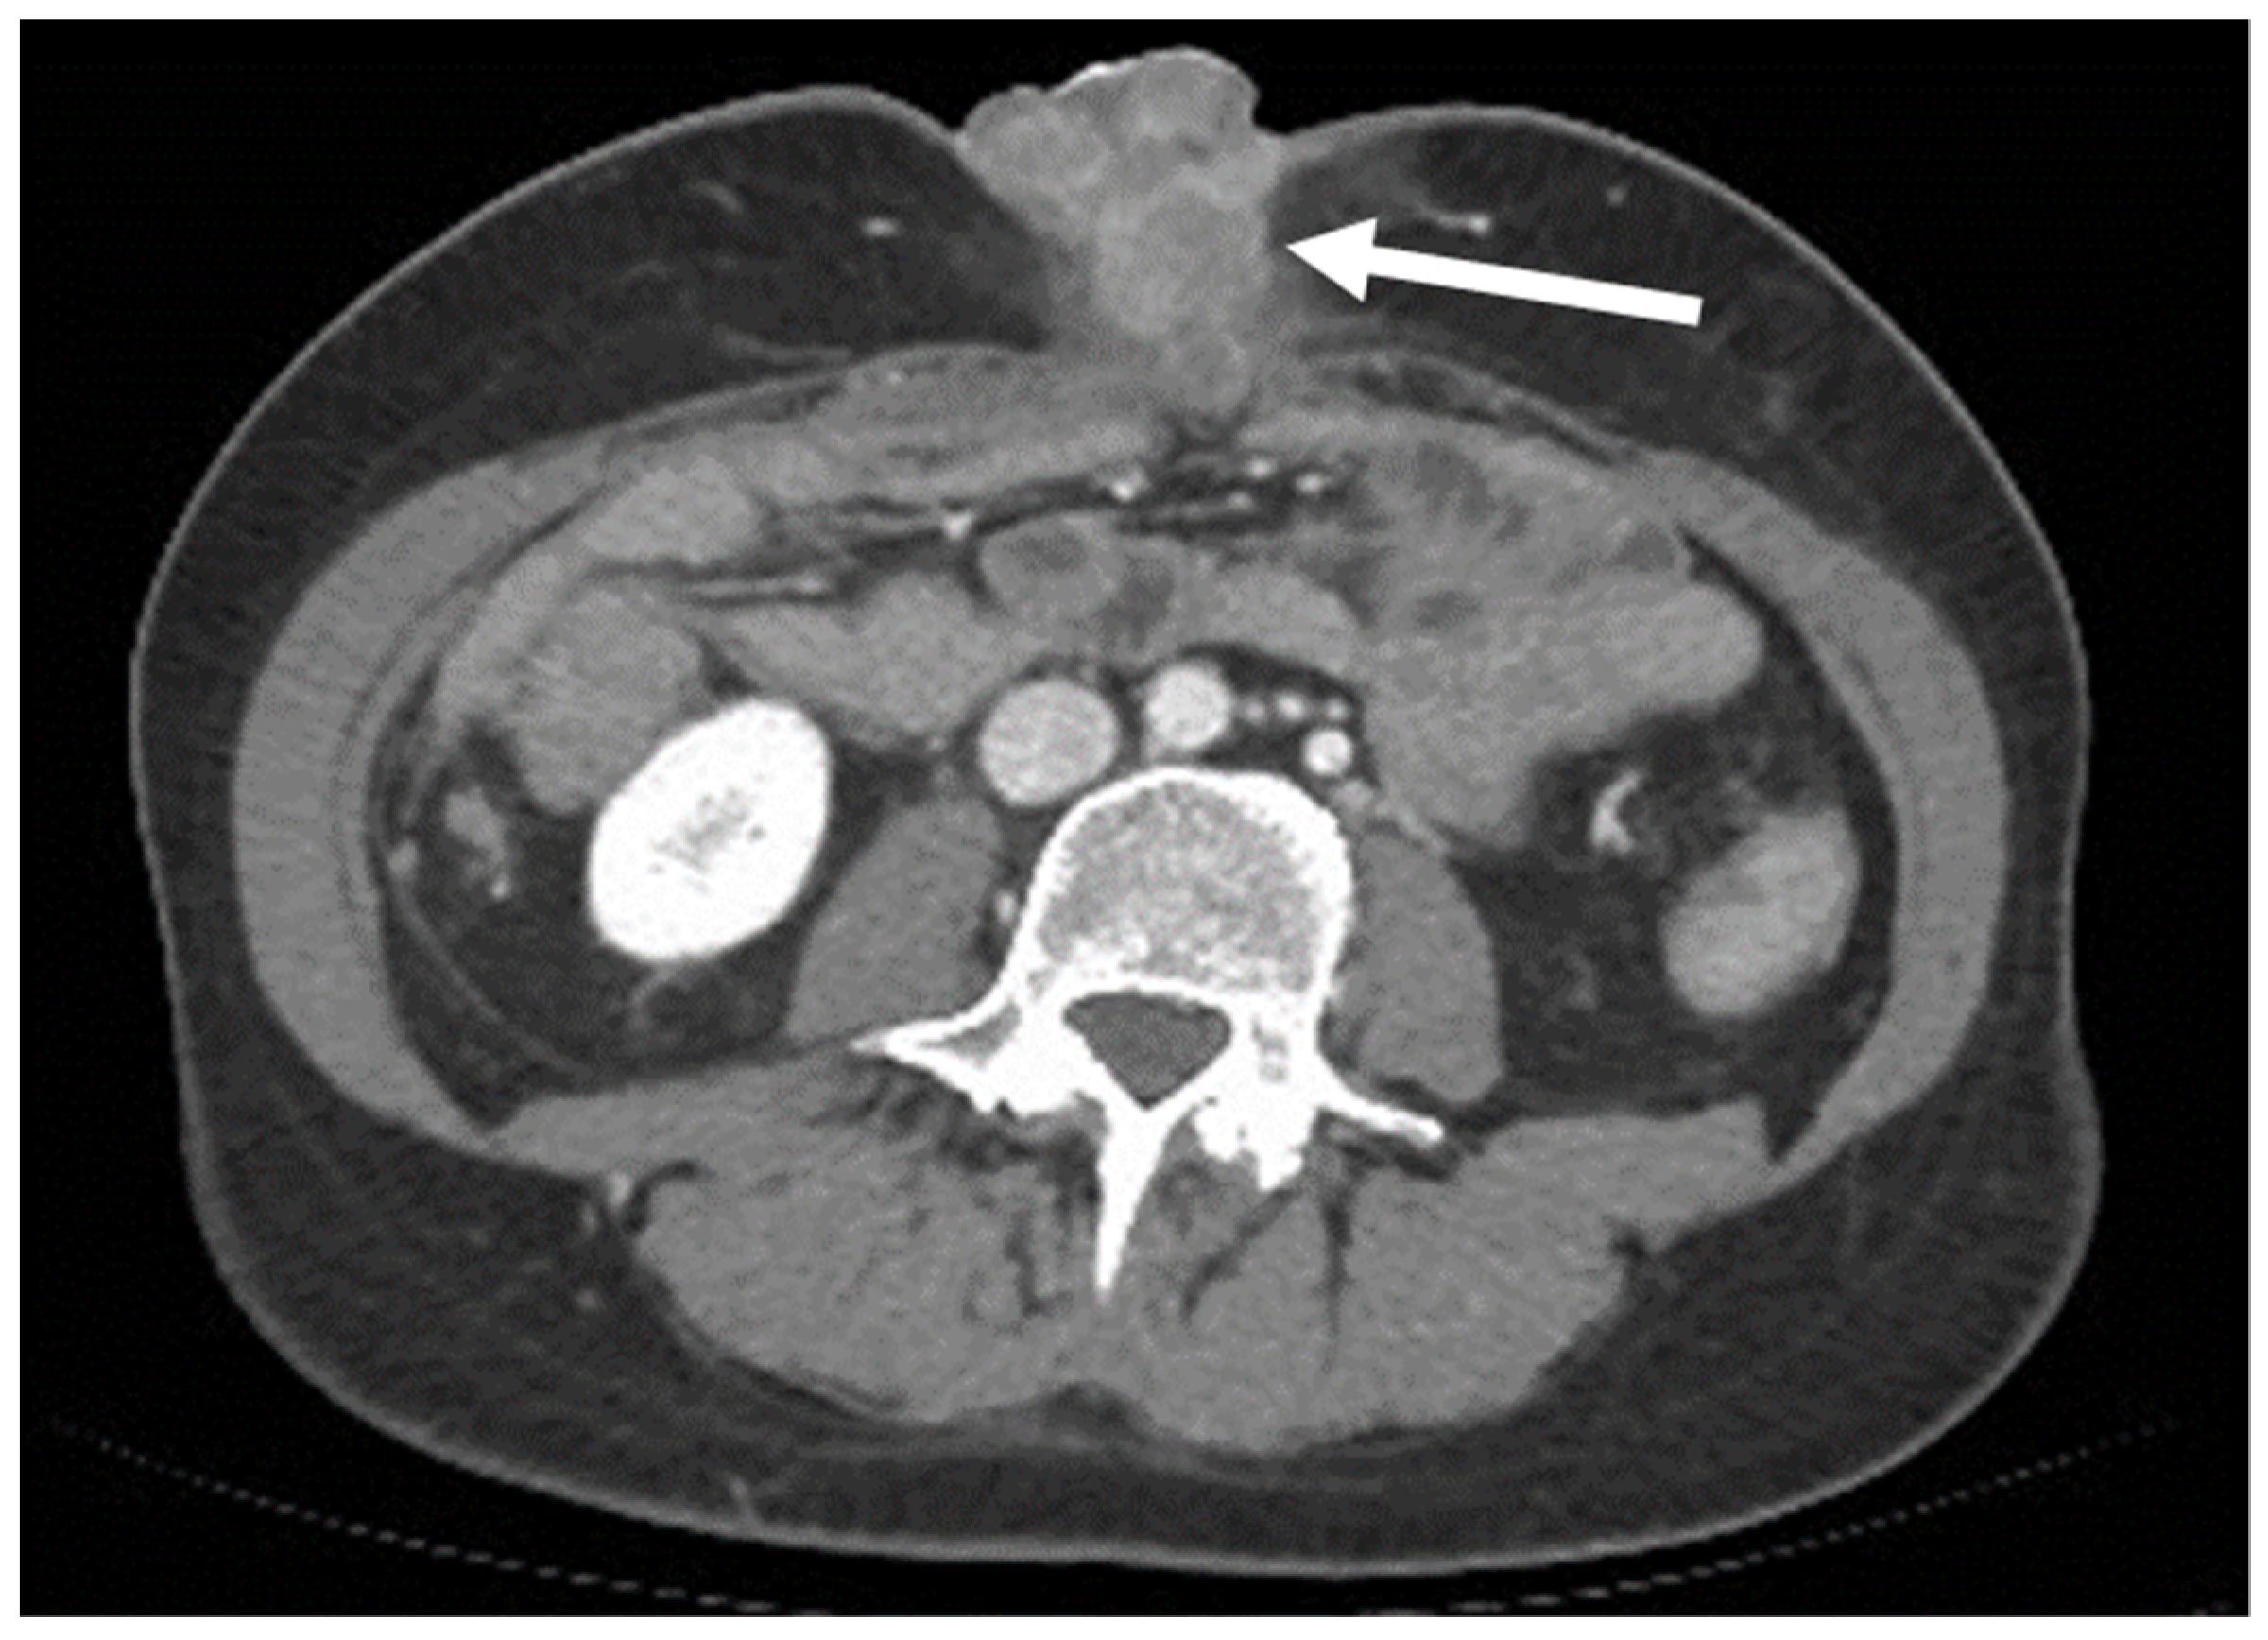

- Leiomyosarcomas: seen on the abdominal wall as either a primary process or as an extension of an intra-abdominal process [23,24]. Leiomyosarcomas demonstrate heterogeneous attenuation and signal intensity, with irregular peripheral enhancement and enhancing solid portions, mixed with hemorrhagic and necrotic areas [24]. Fatty components are absent (Figure 9) [23,24].